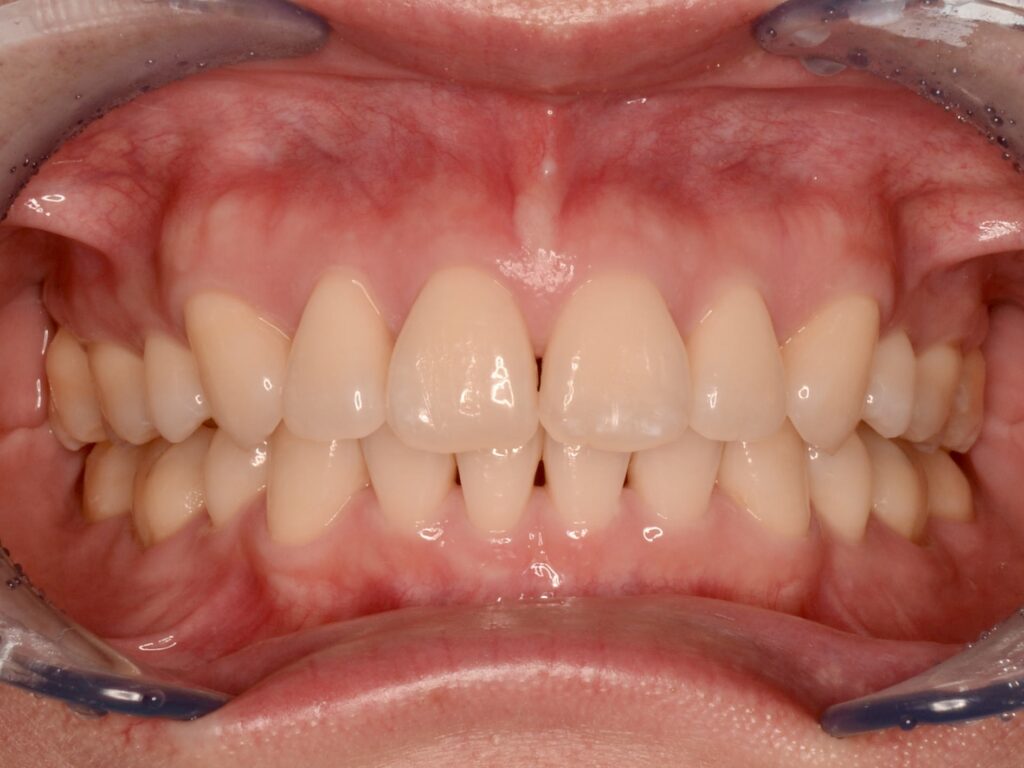

矯正治療の症例